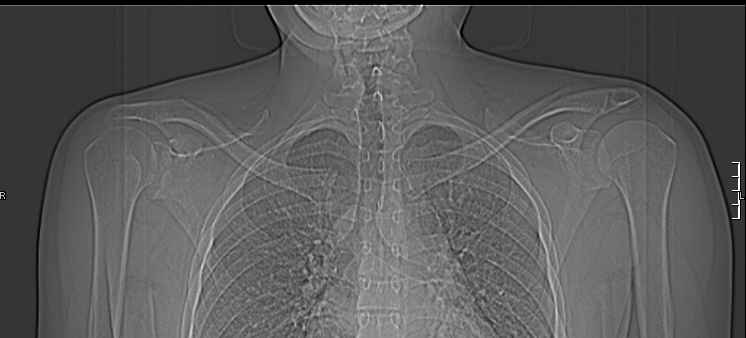

Задний вывих плеча действительно есть. Такой вариант вывиха по прямой рентгенограмме действительно не бросается в глаза. Травматологи-ортопеды в Молдавии есть.

Точен ли диагноз? Неодходимо ли оперативное вмешательство? Это очень важно для меня, поскольку я из Молдавии, а у нас специализированных учреждений нет. Даже предположительный диагноз поставили спустя год после травмы, направив на томографию (по обычным рентгеновским снимкам определить ситуацию не могли).